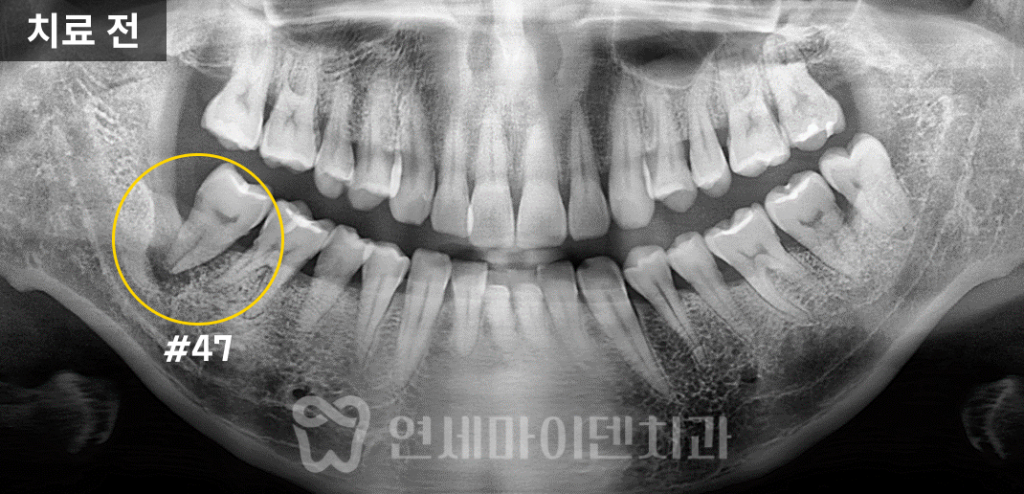

아래쪽 어금니가 심하게 흔들리고 있었고,

손으로 살짝만 힘을 줘도 빠질 정도로

뼈가 많이 녹아 있었던 상태였습니다.

문제는 발치를 하더라도

하치조 신경관과 너무 가까운 위치이기 때문에임플란트를 심기 어렵다는 진단을

타원에서 받으신 겁니다.실제 엑스레이 상으로도

치아 뿌리 주변의 치조골이 까맣게 소실돼 있었고,신경관이 바로 인접해 보이는 모습이 관찰되었습니다.